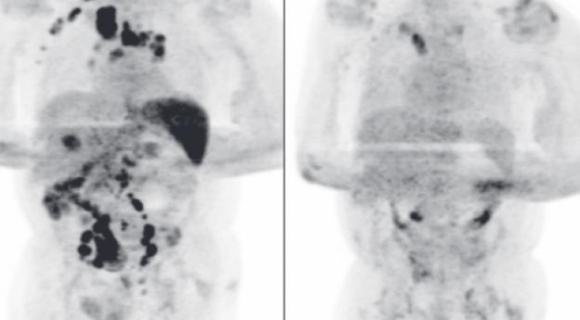

Tình trạng u lympho Hodgkin của người đàn ông này đã thuyên giảm đáng kể sau khi mắc Covid-19/CHỤP MÀN HÌNH TẠP CHÍ HUYẾT HỌC ANH

Ngay sau khi được chẩn đoán mắc bệnh ung thư giai đoạn 3 và có nhiều khối u trên khắp cơ thể, bệnh nhân này mắc Covid-19 và phải nhập viện trong 11 ngày. Sau khi ổn định, bệnh nhân được cho về nhà để tiếp tục hồi phục.

Các kết quả chụp chiếu và xét nghiệm của bệnh nhân này 4 tháng sau đó cho thấy nhiều khối u hầu như đã biến mất. Trong thời gian nằm viện vì Covid-19, bệnh nhân không được điều trị bằng cách phương pháp có thể dẫn đến kết quả này. Bệnh nhân cũng không được điều trị ung thư do bị suy thận.